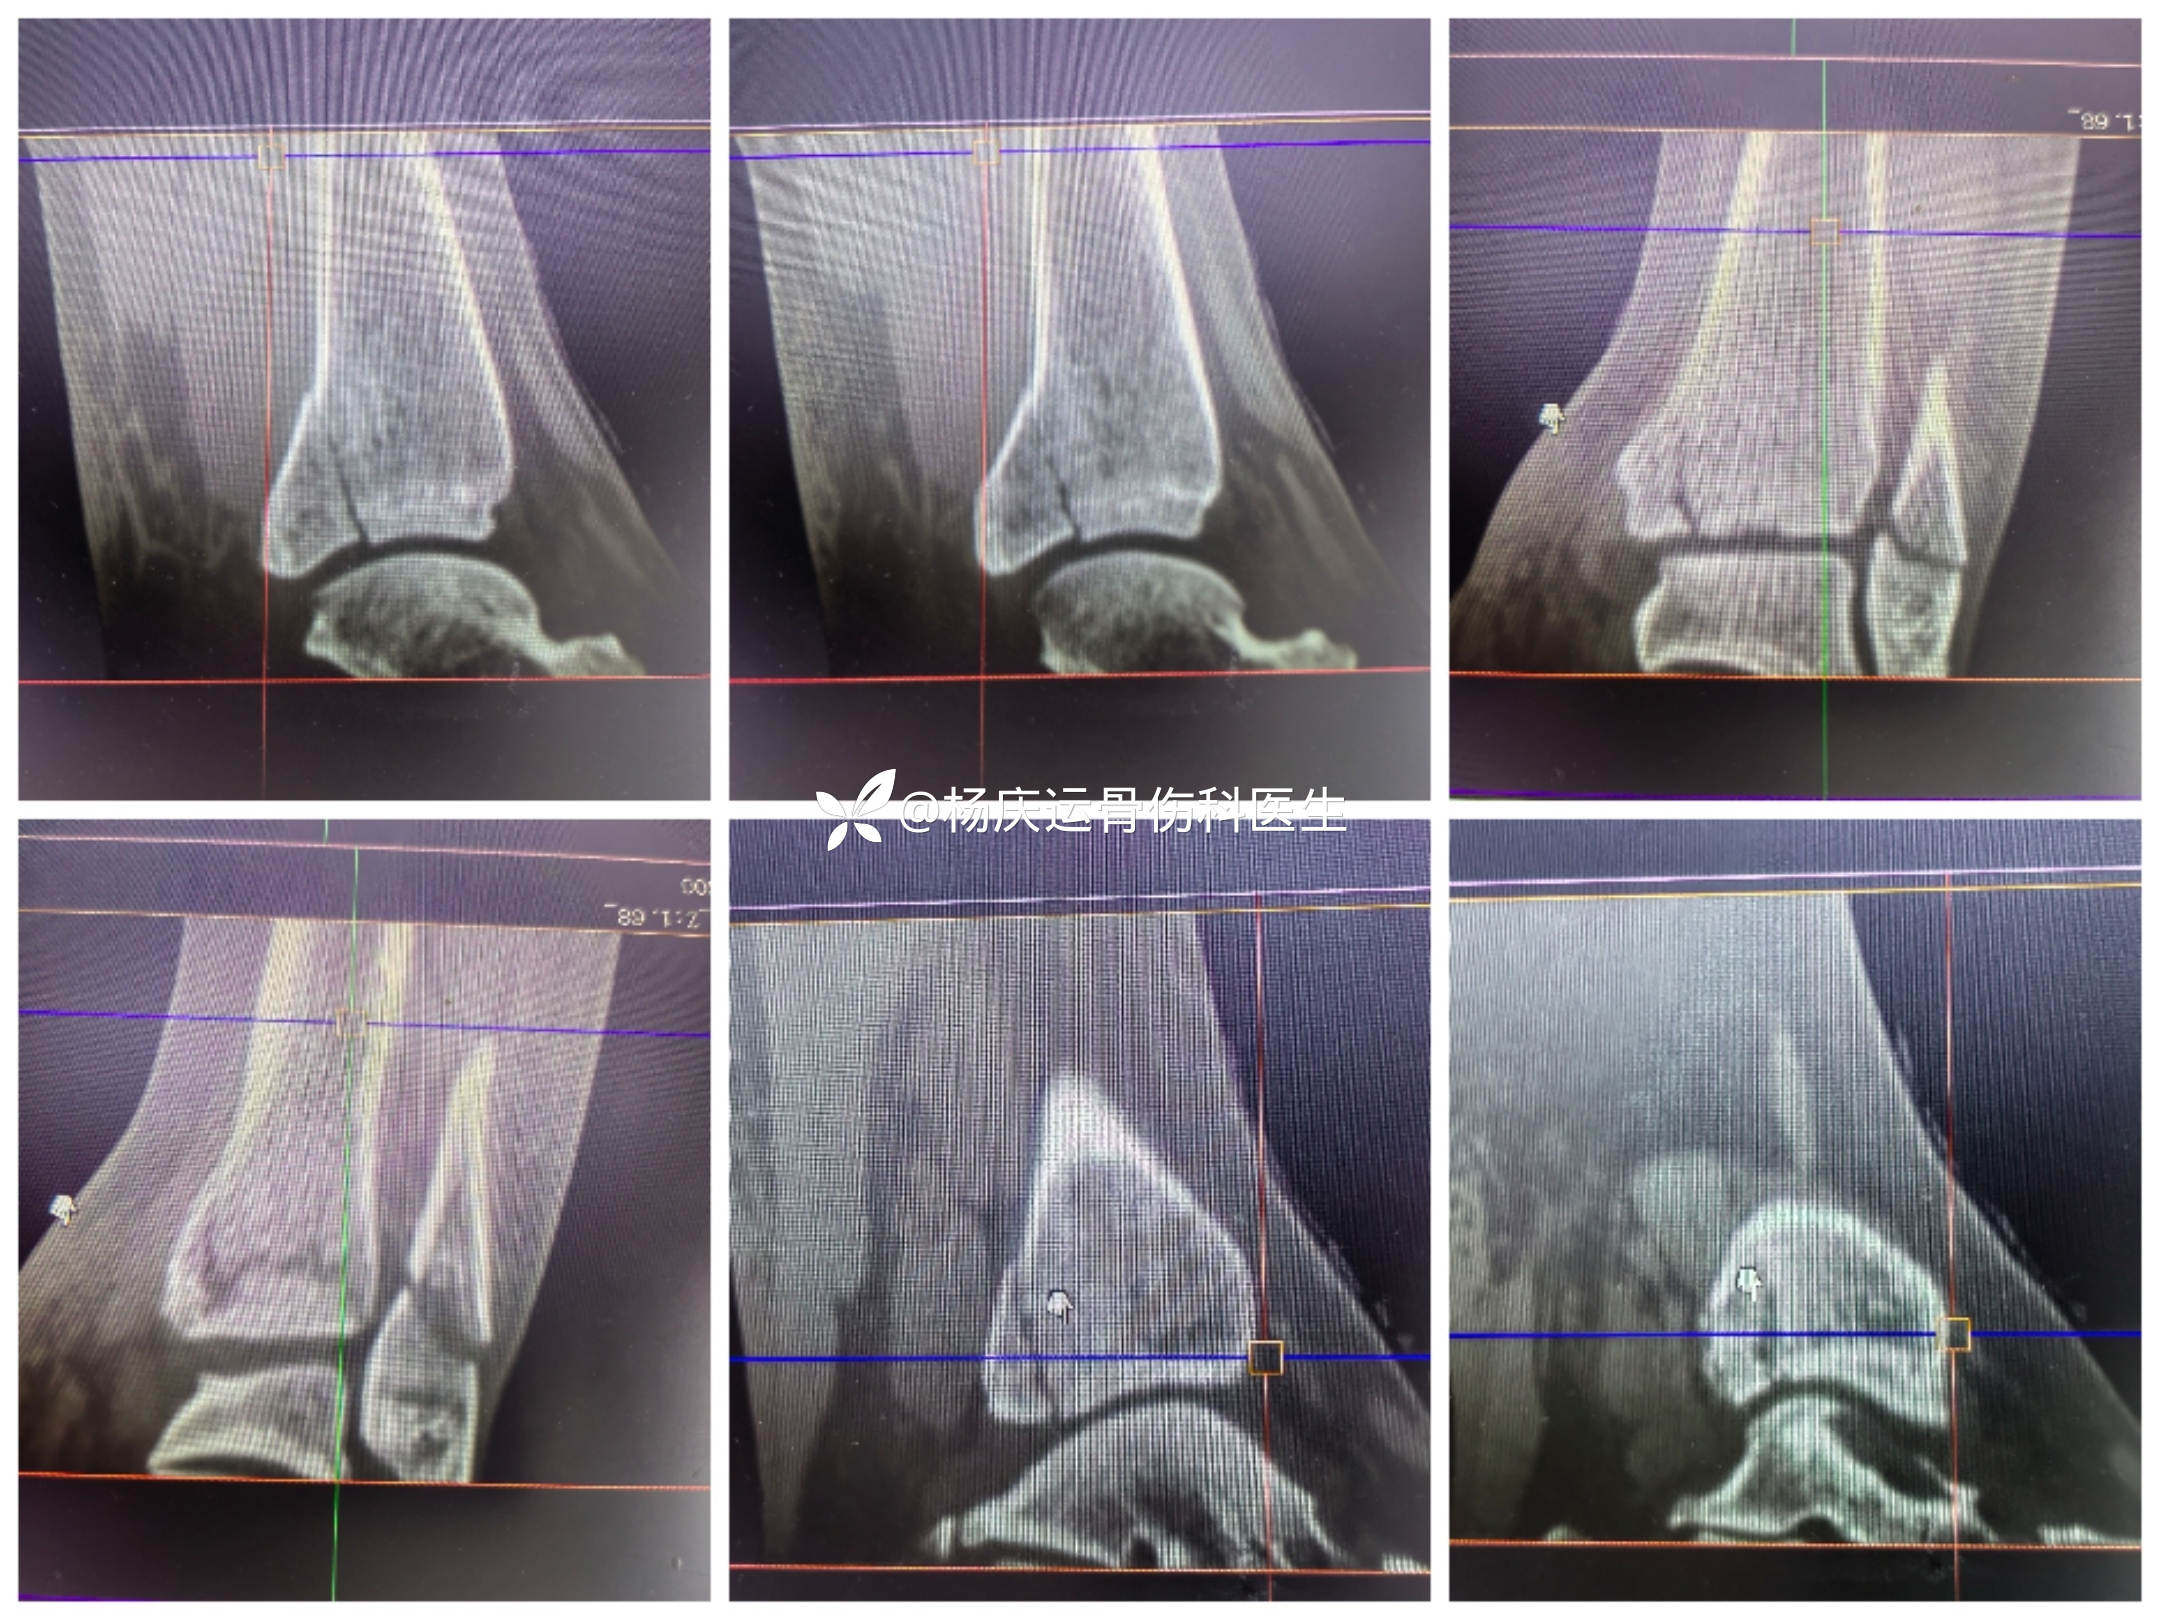

首诊三维CT

3天复查CT

关节面台阶约1.0mm